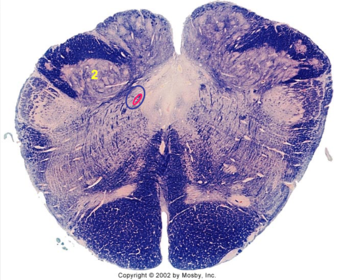

| Nucleus gracilis | |

| Nucleus cuneatus | |

| Fasciculus gracilis | |

| Fasciculus cuneatus | |

| Internal acruate fibers | |

| Lateral (external/accessory) cuneate nucleus | |

| Medullary pyramids | |

| Hypoglossal nucleus | |

| Hypoglossal nerve | |

| Dorsal motor nucleus of X | |

| Nucleus ambiguus | |

| Solitary tract | |

| Solitary nucleus | |

| ALS | |

| Medial lemniscus | |

| Medial longitudinal fasciculus | |

| Spinal tract of V | |

| Spinal nucleus of V | |

| Lateral (external, accessory) cuneate nucleus | |